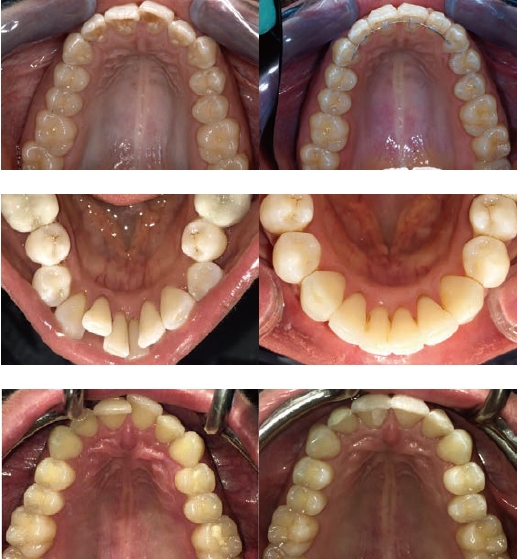

インビザラインGoは、前歯から小臼歯までの歯並びを整える「部分矯正」に特化したマウスピース型矯正治療です。透明なマウスピースを使用するため、目立ちにくく、日常生活に支障をきたしにくいのが特徴です。軽度の歯並びの乱れに対応し、短期間・低価格で理想のスマイルを目指せます。